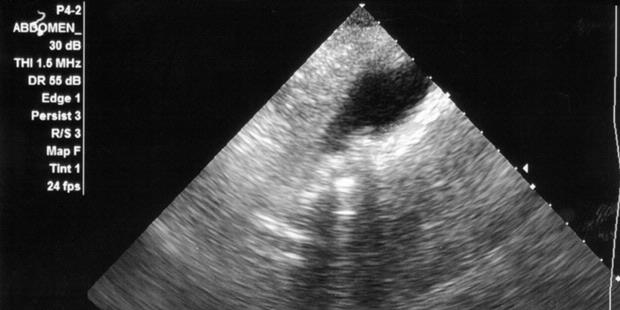

Nyeri karena adanya batu kandung empedu berlangsung beberapa saat dan berulang (kolik bilier), biasanya nyeri tersebut dapat menjalar ke punggung belakang. Untuk mengetahui penyebab dari nyeri ulu hati tersebut perlu dilakukan USG abdomen. Melalui pemeriksaan USG abdomen dapat diketahui apakah ada peradangan baik akut maupun kronis pada kandung empedu tersebut. Selain itu melalui pemeriksaan USG juga diidentifikasi adanya batu pada kandung empedu. Pemeriksaan USG abdomen juga dapat mengevaluasi saluran empedu, bisa mengidentifikasi adanya pelebaran saluran empedu.